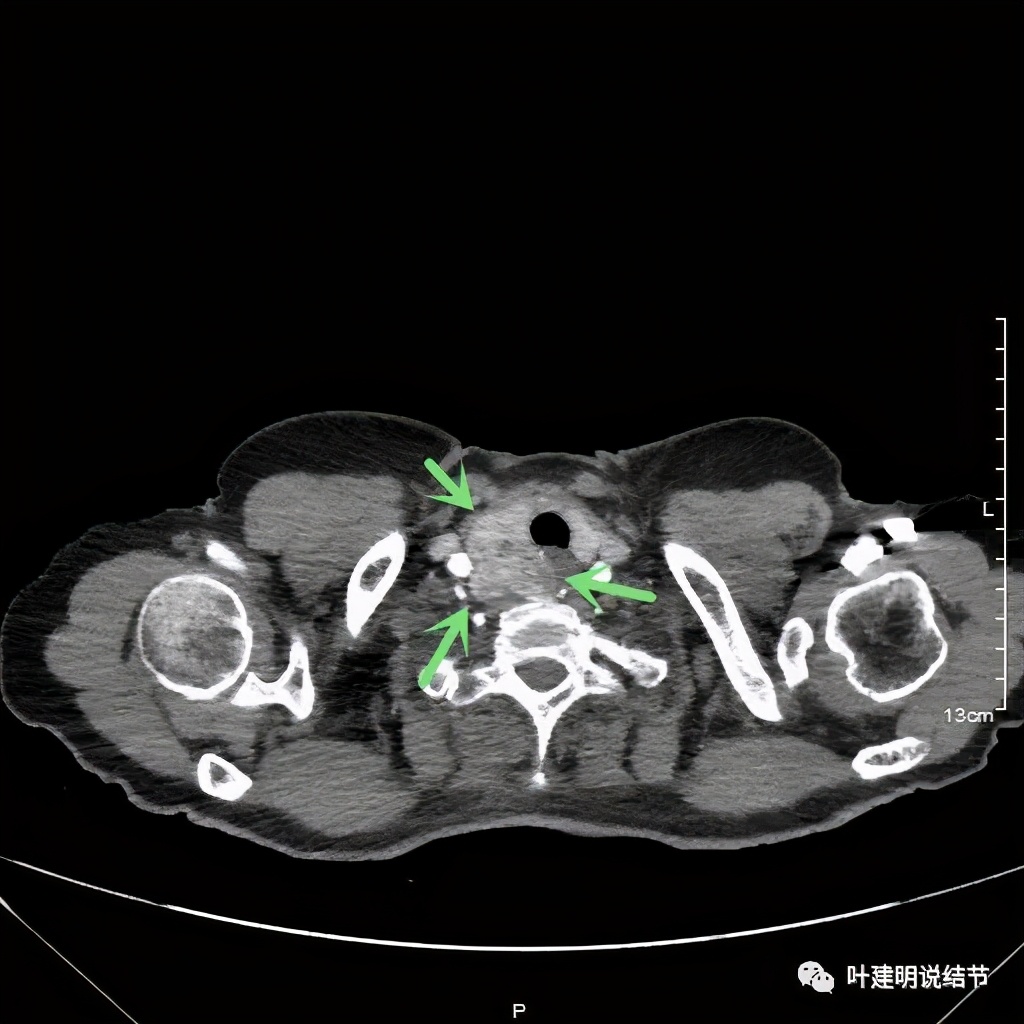

金华地区的某A,今年已经76岁了,近段时间觉得胸闷不适,还有刺激性咳嗽,总是不会好,到当地医院查了胸部CT,发现是纵隔肿瘤。当地医生建议她到金华市中心医院做下气管镜下穿刺活检,以明确肿瘤性质。因为认识我们医院的某外科主任,所以又建议她来找我,结果我一看她从当地带来的片子,是纵隔内巨大的占位,与气管关系密切,位于气管右侧、食管右前侧、上腔静脉左侧、无名静脉后侧,被诸多结构包绕着,而且肿瘤密度不均,靠气管与无名静脉侧间隙不清,首先考虑纵隔内恶性或交界性肿瘤,由于年纪这么大,手术风险较高,若与气管有侵犯,则手术达不到根治,我也觉得应该先行经气管镜下的穿刺活检,明确病理后再考虑怎么办。所以让某A住到呼吸内科去,打算行气管镜下纵隔肿瘤穿刺活检。因当地的片子扫到胸顶部为止,没有做增强,我们先取本院增强片子上达胸顶,下达肿瘤下缘的范围来看看肿瘤的样子:

胸顶就开始有肿瘤了,黄色示受压迫移位的气管,红色示肿瘤

上图红色示肿瘤,黄色示气管,粉色示肿瘤与气管关系密切,而且肿瘤密度不均杂乱

上图红色示肿瘤,黄色示气管,而且肿瘤密度不均杂乱